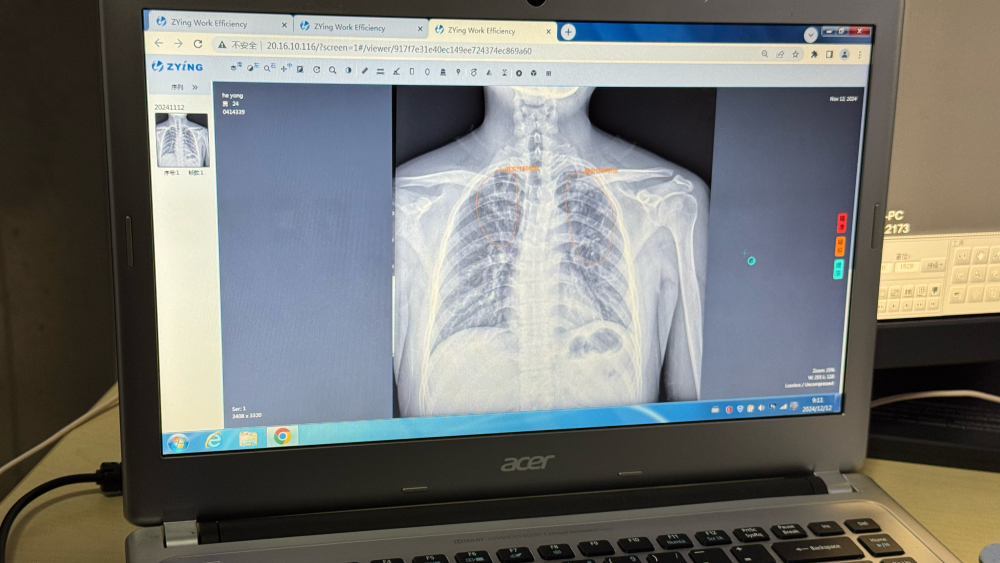

记者在江苏省走访时看到,通过将人工智能阅片模型装入影像科云平台,全省所有公立医院和部分民营医院的医疗机构实现互联互通,能够快速筛查患者胸片可疑病灶,并生成自动化报告。

“AI赋能有效提高筛查效率和诊断精确度,尤其是在基层医疗机构发挥了重要作用。”江苏省疾控中心慢性传染病预防控制所所长竺丽梅说。

江苏省昆山市第一人民医院锦溪分院放射科AI云平台阅片系统。新华社记者顾天成 摄

从AI筛查到全程数据管理,再到全自动一体化微型核酸检测系统,科技不仅优化了传统筛查流程,也为“无结核社区”建设、实现“首诊即确诊”提供了创新解决方案。

江苏省昆山市第一人民医院锦溪分院放射科主任汤青燕表示,AI技术不仅能为肺结核筛查提供支持,还促进了包括肺炎、肺癌在内的多种肺部疾病早期发现和诊断。